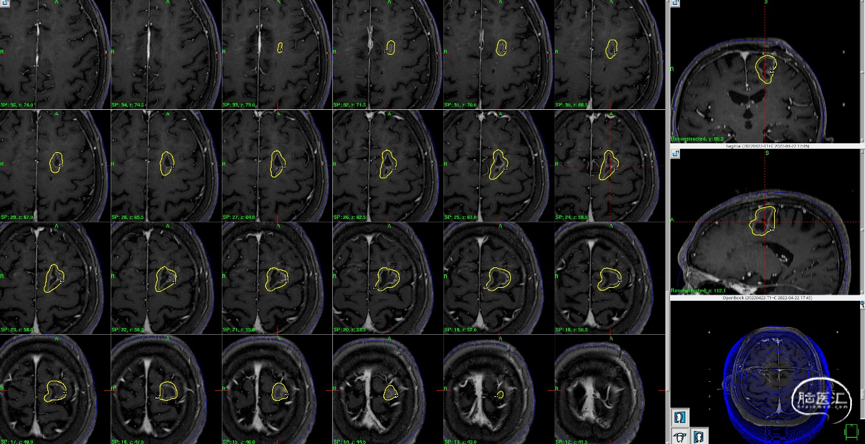

术前影像检查

头颅MRI:显示左额、右侧侧脑室壁占位

1. 较大左侧额上回后部占位,向后挤压中央前回,增强后有明显强化。

2. 右侧侧脑室占位,增强后有明显强化。

磁共振MRI定位扫描(T1增强序列,1mm轴位连续断层薄扫)。

磁共振MRI定位扫描(T2平扫,2mm轴位连续断层+T1增强序列,1mm轴位连续断层薄扫)。

制定立体定向伽玛刀治疗计划(术中薄扫核磁扫面共发现4个病灶,除术前的2个病灶外,还发现2个小病灶);

1)左额囊性病灶治疗计划(分期治疗):边缘剂量11Gy(55%,中心20Gy),照射体积:16.563cm3。